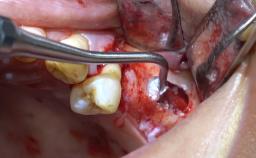

- Details of surgical techniques for SFE

- Management of complications